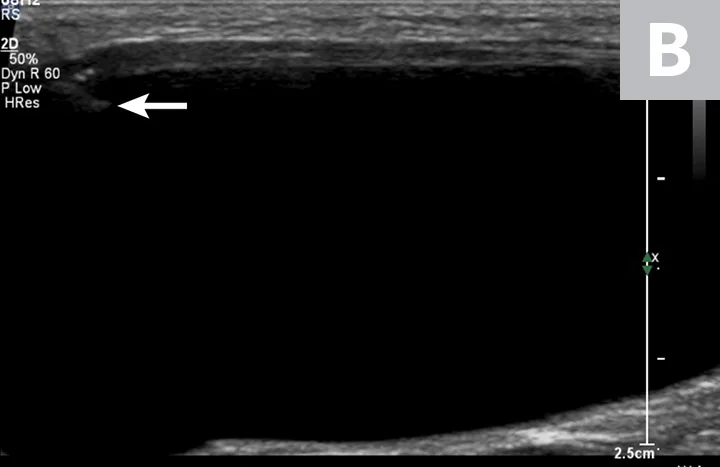

Cystocentesis is often performed with ultrasonographic guidance, although this is not required (ie, blind cystocentesis). Using ultrasonography can help direct visualization of the needle in the urinary bladder lumen, avoiding iatrogenic damage of surrounding structures (Figure 1). The relative size of the bladder, echogenicity of its contents, and any obvious structural abnormalities can also be observed. A primary advantage of blind cystocentesis is that it does not require special equipment. Cystocentesis can be challenging to perform in patients that have abdominal effusion and should be performed with ultrasonographic guidance in such cases.

FIGURE 1

Ultrasonographic image showing the cranial aspect of the urinary bladder (A), identified just before ultrasound-guided cystocentesis. It is important to adjust the depth of the image so that the urinary bladder is focused and to consider the depth of the urinary bladder using a machine scale that should be present on the ultrasound screen; in smaller patients the needle may only be partially inserted and not reach the hub (B; arrow).